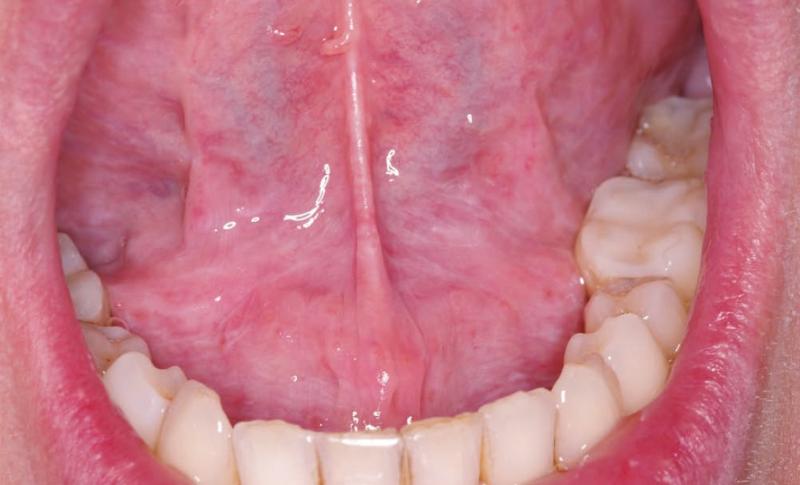

CASO CLÍNICO LX

Descripción del caso Un varón de 57 años refiere que hace seis meses empezó a sentir molestias en el lado derecho de la lengua, que han ido en aumento y actualmente le...